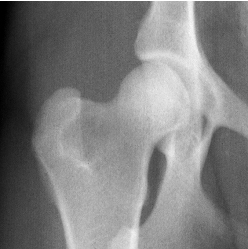

當前主流的骨關節保健品主要有葡萄糖胺(glucosamine)、軟骨素(chondroitin),以及有機硫同化物(methyl-sulfonyl-methane,即MSM)等。葡萄糖胺和軟骨素在骨關節處形成蛋白聚糖,吸收水分和體液,使關節運動時得到潤滑,而MSM則是止痛劑。這些都僅僅是緩解症狀,很難治本。美國UCLA骨科專家臨床研究表明,一般葡萄糖胺要四、五年才能修復軟骨;而以Kolla2(Ⅱ型骨膠質)為主方,輔以上葡萄糖胺、MSM等,則大大縮短消除關節疼痛和修復軟骨的時間。研究證明服用Kolla2(Ⅱ型骨膠質)六周后,患有髖關節發育異常的犬科動物恢復了正常運動功能,隨後的X-射線檢查表明其髖關節軟骨恢復正常。